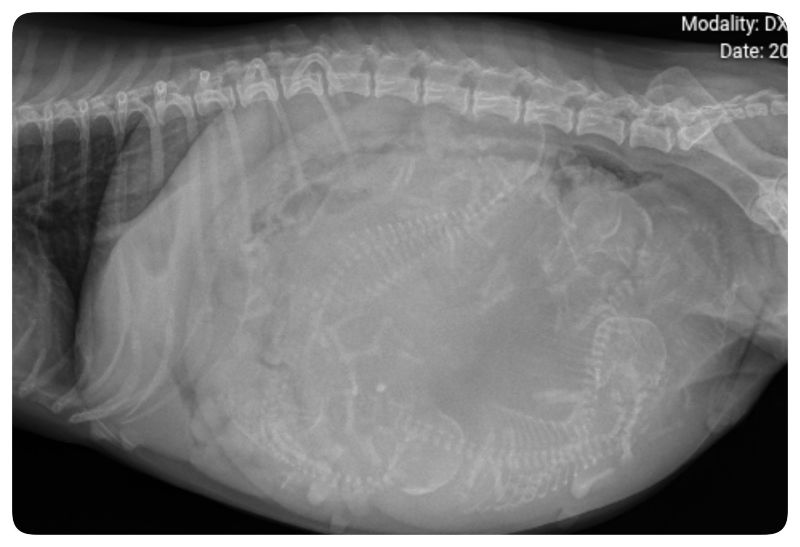

![]()

Fenja wird jetzt geröngt um zu sehen ob was im Geburtskanal liegt.

15h, 5 Welpen sind noch drin, herzschläge sind gut von den Welpen, Fenja bekommt jetzt Oxytozin und Stärkung gespritzt, 45 min warten wir dann noch ob sie es aus eigener Kraft schafft.